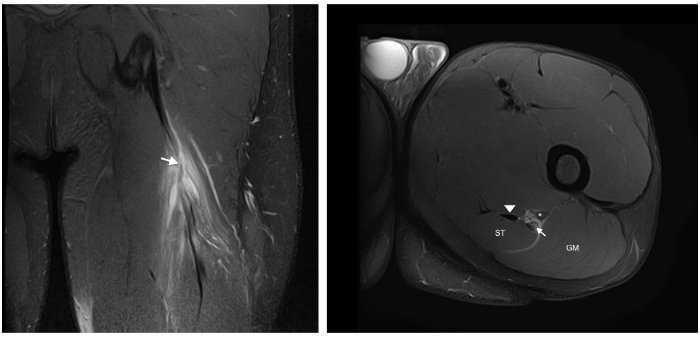

Figura 2 Las imágenes coronal y axial en T2 con saturación grasa del isquiotibilal izquierdo muestran cambios de espesor e intensidad de la señal del tendón libre (flecha), contornos borrosos y discontinuidad ampliada hasta UMT proximal. Existe retracción distal leve de UMT proximal. Vientre del músculo semitendinoso (ST), glúteo mayor (GM), tendón semimembranoso (punta de flecha) y nervio ciático (*).